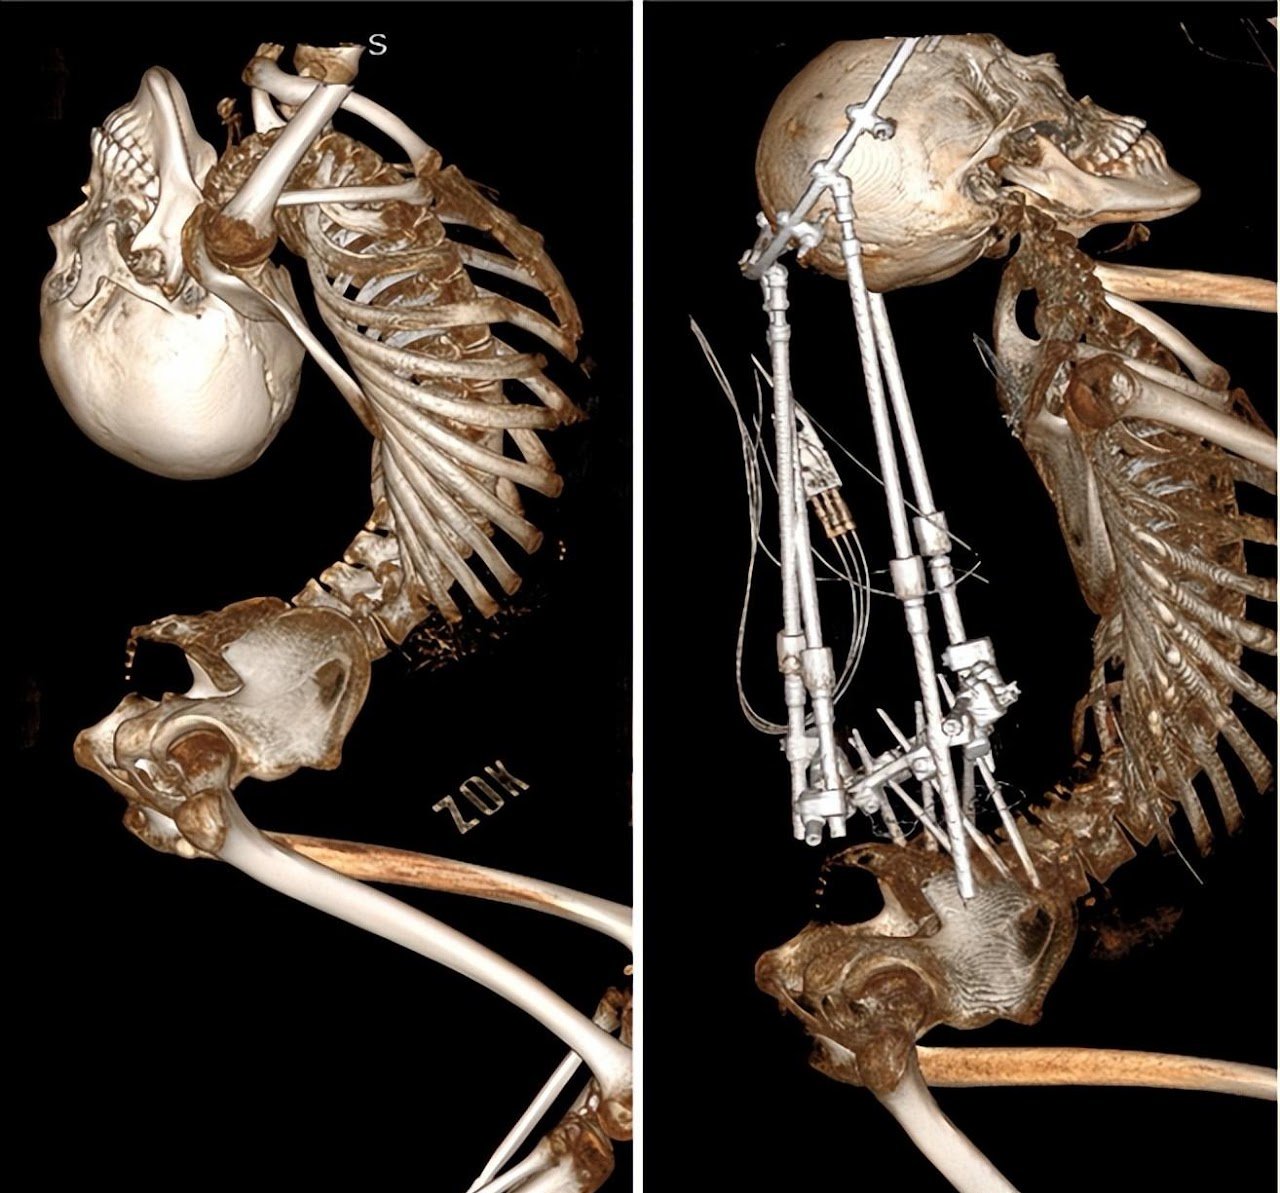

Jól látható a változás a röntgenfelvételen ((Fotó: Peking University Health Science Centre)

A röntgenfelvételeken jól látszik, milyen hihetetlen munkát végeztek az orvosok a fiú alakjának korrigálása érdekében. Október 8-án aztán eltávolították a fejmerevítő gyűrűt, amelyet csaknem öt hónapon át viselt, így Jiang a korábban teljesen hátrahajtott fejét végre függőleges pozícióban tudja tartani, le tud ülni egy székbe, és látja a körülötte lévő embereket.